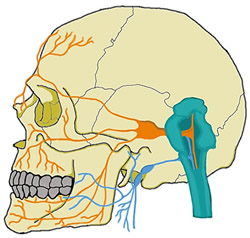

En los últimos años se han incrementado los estudios de dispositivos de estimulación nerviosa no invasivos, buscando reducir los síntomas de los pacientes con una baja tasa de complicaciones. Dentro de estos se incluyen los dispositivos de estimulación cervical izquierda del nervio vago (NX), los cuales tienen un objetivo en epilepsia y migraña, pero ha surgido cada vez más evidencia de control en dolor trigeminal (3) fundamentados en la cercanía a anatómica y posibilidad de conexiones centrales de estos dos nervios (Figura 1). Existen diferentes revisiones que tienen hipótesis de conexiones entre el nervio trigémino y el vago, lo que se conoce como el sistema trigémino-vagal (Figura 2). En un estudio reciente, publicado en el 2022, Peng y cols. (4) evaluaron la plausibilidad anatómica del sistema trigémino vagal. Realizaron un estudio entre 2019 y 2020 con voluntarios sanos en 3 etapas: una exploratoria inicial, una segunda etapa para la validación y la comparación del efecto de la estimulación vagal no invasiva (EVNI) en las diferentes ramas trigeminales y una tercera de la comparación entre intervenciones unilaterales y bilaterales con su impacto sistémico en la frecuencia cardiaca.

Fig. 1. Distribución cráneo facial del nervio vago (azul) y nervio trigémino (naranja).